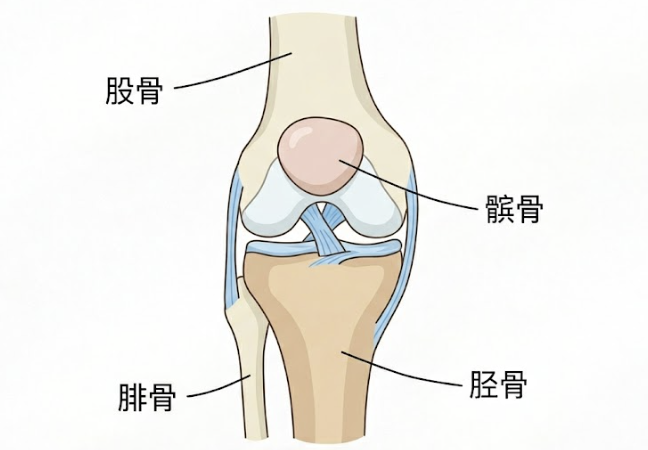

膝盖周围其实隐藏着三套核心系统,它们就是:关节软骨、韧带、肌肉。

它们各司其职,共同构筑了膝关节真正的「隐形支架」。想要膝盖稳定、减少损伤,这三大支柱缺一不可!

从解剖结构上看,膝关节其实是一个发育不完全的关节。不像髋关节(大腿根)那样有一个深凹的球窝紧紧扣住,膝盖本质上是两根圆溜溜的长骨(股骨和胫骨)头对头碰在一起。

✨ 膝关节周围,主要有这么4根韧带:前交叉韧带、后交叉韧带、内/外侧副韧带。